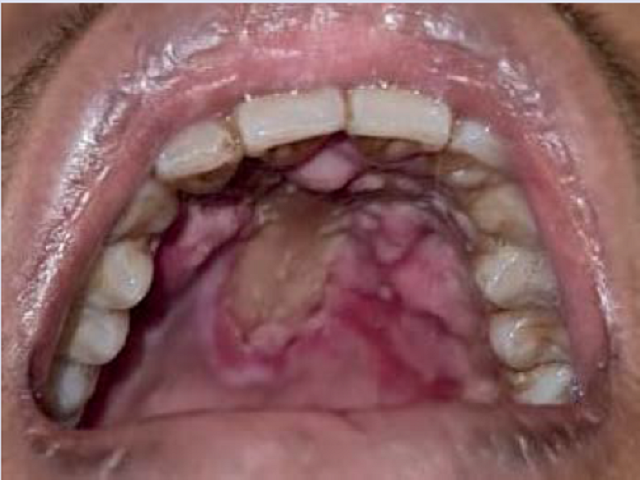

ArticleViewAbstractPharmacognosy Journal,2024,16,5,1143-1149.DOI:10.5530/pj.2024.16.187Published:October 2024Type:Research ArticleAtypical Manifestation of Oral Candidiasis in Patient with Aplastic AnemiaPraf Nahlalogi, and Bramantono Praf Nahlalogi1,2, Bramantono1,2,3* 1Department of Internal Medicine, Dr. Soetomo General Academic Hospital, Surabaya, INDONESIA. 2Department of Internal Medicine, Faculty of Medicine, Universitas Airlangga, Surabaya, INDONESIA. 3Division of Tropical and Infectious Disease, Department of Internal Medicine, Dr. Soetomo General Academic Hospital, Surabaya, INDONESIA. Abstract:Candidiasis is an opportunistic fungal infection predominantly caused by Candida species, which can manifest in immunocompromised individuals such as those with aplastic anemia. Aplastic anemia, characterized by bone marrow failure, significantly increases susceptibility to infections, with fungal infections being a leading cause of mortality. Oral candidiasis is one of the most common manifestations, and it typically presents as white pseudomembranes. However, atypical presentations can occur. We report a case of a 26-year-old male with aplastic anemia who presented with general weakness, fever, and painful swallowing. On examination, a blackish plaque was observed on his palate. Laboratory tests, including palatal tissue smear, histological examination, and culture, confirmed an infection of Candida tropicalis. This unusual blackish manifestation of oral candidiasis, resembling mucormycosis, has not been previously described in the literature. The patient was treated with intravenous fluconazole, leading to complete resolution of the oral lesions within 11 days. Through this case, we underscore the importance of recognizing atypical presentations of common infections, particularly in immunocompromised patients, and highlight the need for thorough diagnostic evaluation to guide appropriate antifungal therapy. Keywords:Aplastic anemia, Atypical presentation, Black oral thrush, Candida tropicalis, Oral candidiasisView:PDF (891.31 KB) PDF Images Clinical resolution after 11 days of fluconazole injection ‹ Clinicopathological Analysis of Mucinous Ovarian Tumors at a Single Center in Indonesia, 2019-2023 up Exploration of Adolescent Knowledge Experiences and Efforts to Identify Interventions on the Use of Digital Technology Information Media to Increase Knowledge related to HIV/AIDS Prevention ›